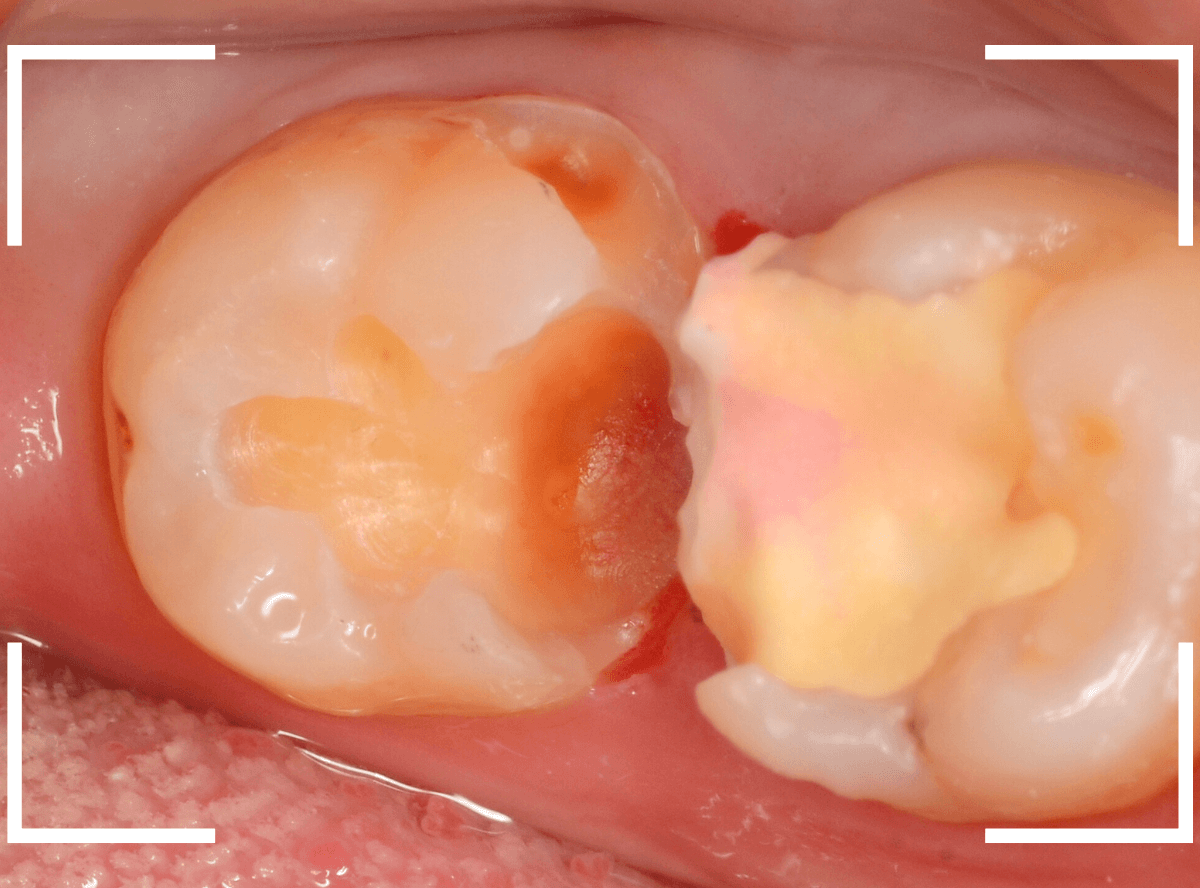

Case.21 神経に達しそうな2本の大きな虫歯

上の小臼歯の側面が明らかに虫歯になっている患者さんです。

患者さんは特に症状を感じてなさそうですが、恐らくは中で大きな虫歯になっているでしょう。

このように、自覚症状からだけでは虫歯の状況は診できません。

レントゲン写真で確認します。

青い線が歯の神経、赤い線が虫歯と思われる部分です。

2本とも、神経に達してしまいそうな大きな虫歯であると思われます。

まず、奥の歯のつめものを外してから、虫歯の治療を開始します。

手前の歯が大きな虫歯が見えてきました。

神経に達してしまいそうな虫歯ですので、ある程度削ったところで、少しずつエキスカという道具で掻き出すようにして、虫歯を除去します。

虫歯は歯を溶かして進行しますので、骨よりも固い歯もちょっと掻き出すとボロボロと崩れるようになってしまっています。

かなり虫歯を除去したところで、手前の歯は神経が顔を出してしまいました(露髄といいます)。

神経を除去する治療が必要かもしれないです。

全ての虫歯を除去したところです。

幸い、後ろの歯は薄皮一枚のところで神経まで達していない虫歯ですんでいましたが、大きな虫歯だった事には変わりありません。

いつものように、神経が痛み出さないように祈りつつ、お薬で保護して経過観察します。

虫歯は症状からだけでは判断できませんが、定期受診によって、このような大きな虫歯の処置は避けられる事がほとんどです。

かならず歯科の定期受診をしてくださいね。